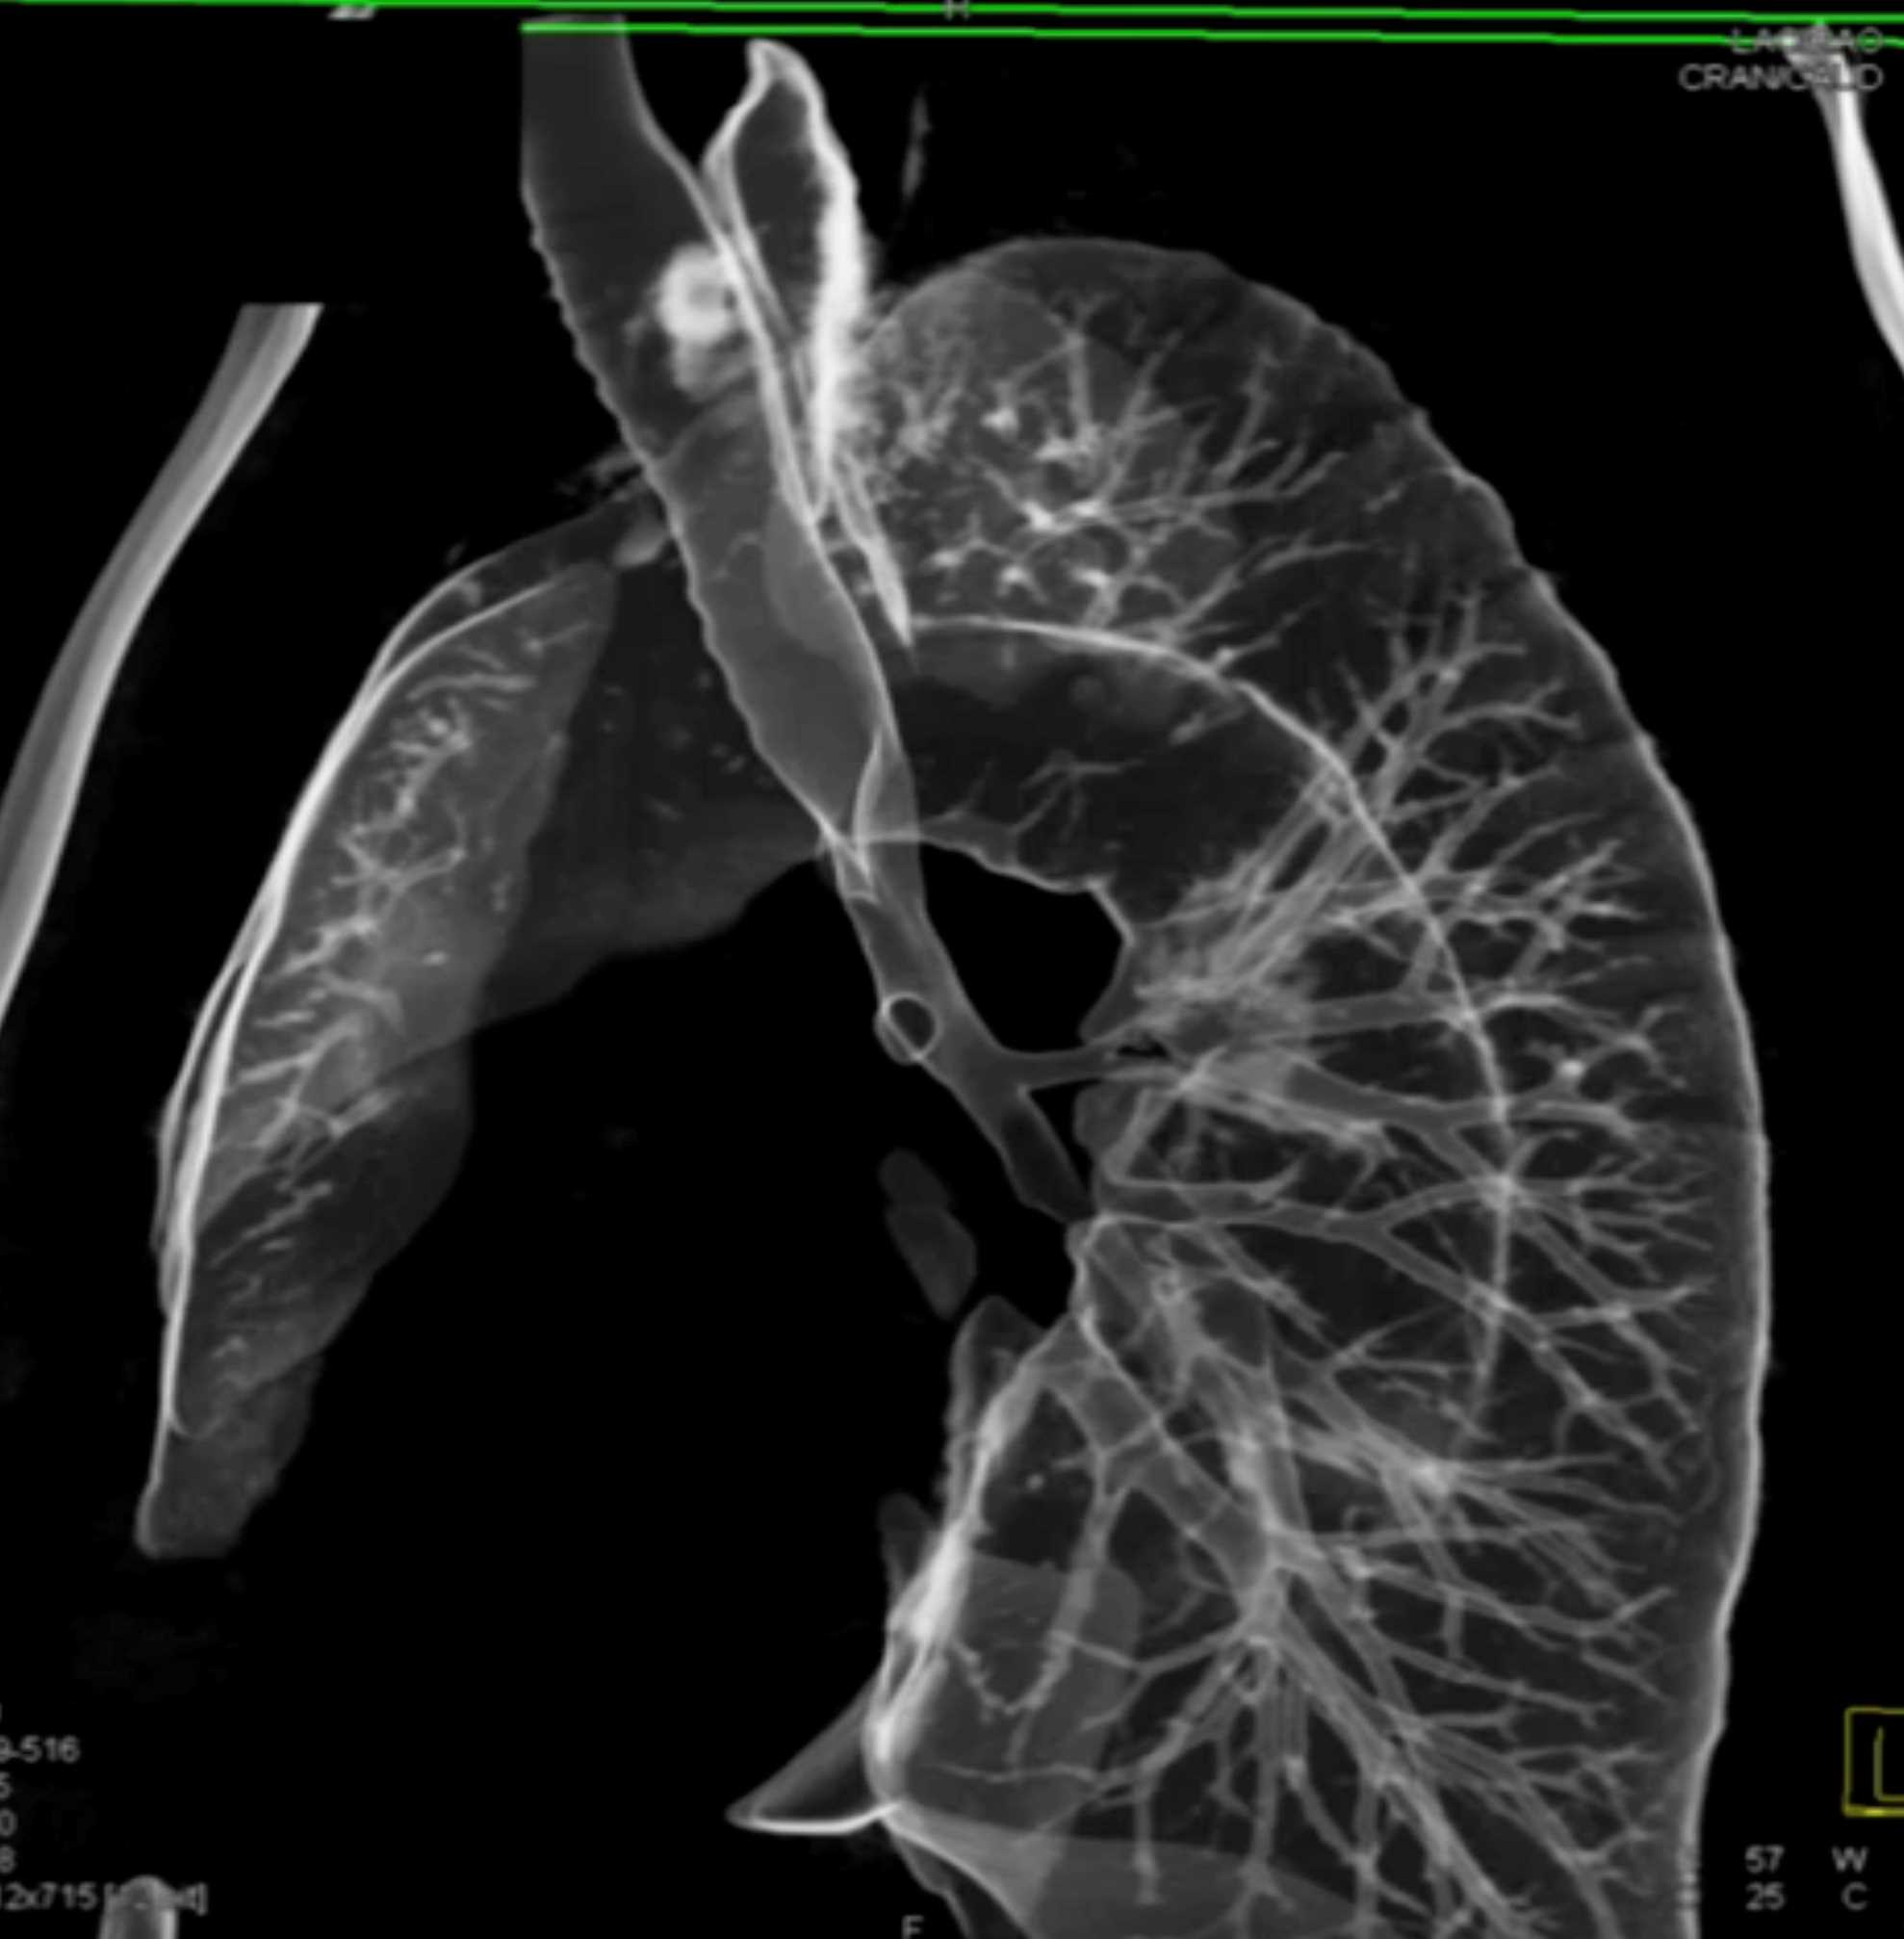

Fibrosing Mediastinitis